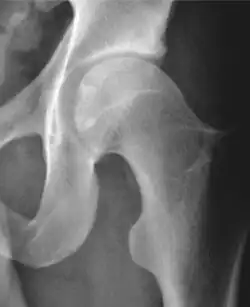

Radiograph of a cam type impingement.

Projectional radiography ("X-ray") is often considered first line for FAI.[10] Anterior-posterior pelvis and a lateral image of the hip in question should be attained.[10] A 45-degree Dunn view is also recommended.[10][19]